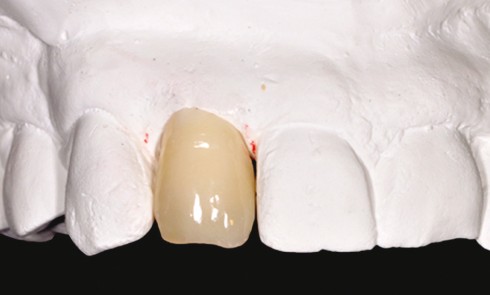

Article réservé à nos abonnés Reconstitution coronoradiculaire adhésive et couronne céramocéramique

Le traitement d’une dent du secteur antérieur nécessite la prise en compte de paramètres biologiques et esthétiques dans les techniques...